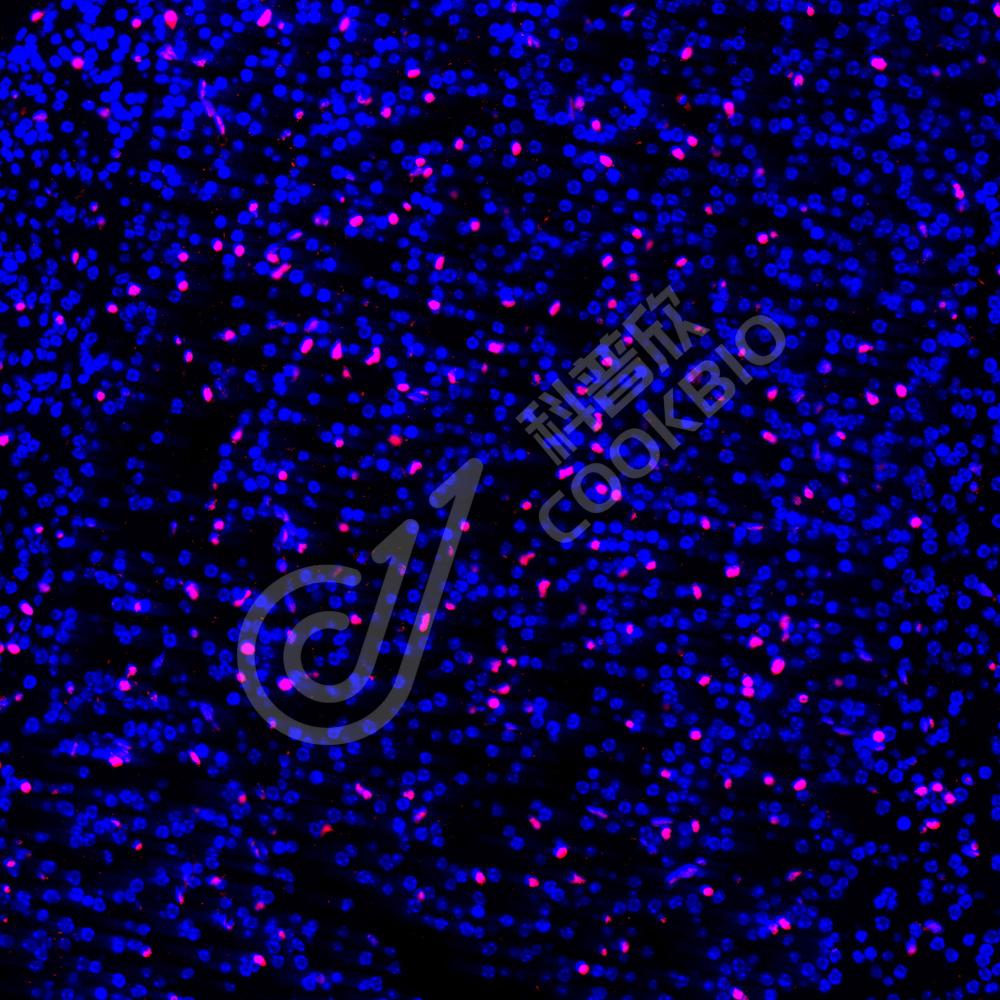

IF检测ZEB1蛋白(货号 K134539)(红色).

样品: 小鼠脑, 4%多聚甲醛 (货号KSG1101) 固定12-24小时.

抗原修复: Tris-EDTA抗原修复液(pH 9.0) (KSG1203), 98℃, 20分钟.

封闭: 3% BSA(货号KSGC305010)的PBS溶液, 室温孵育30分钟.

—抗: 1: 1000稀释, 4℃ 孵育过夜.

二抗: Cy3标记山羊抗兔IgG (H+L) (货号KB63909), 1: 300稀释, 室温孵育1小时.